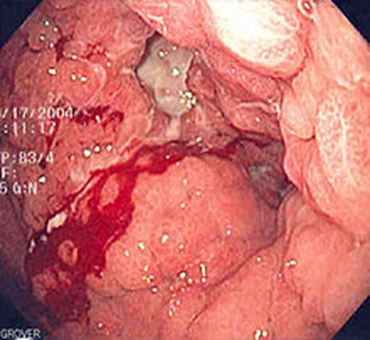

- Chụp CT bụng: U tâm vị dạ dày KT 35x48x52mm thâm nhiễm tổ chức xung quanh, hạch bờ cong nhỏ dạ dày KT 14mm.

Hình 2: Hình ảnh khối u tâm vị dạ dày có thâm nhiễm tổ chức xung quanh